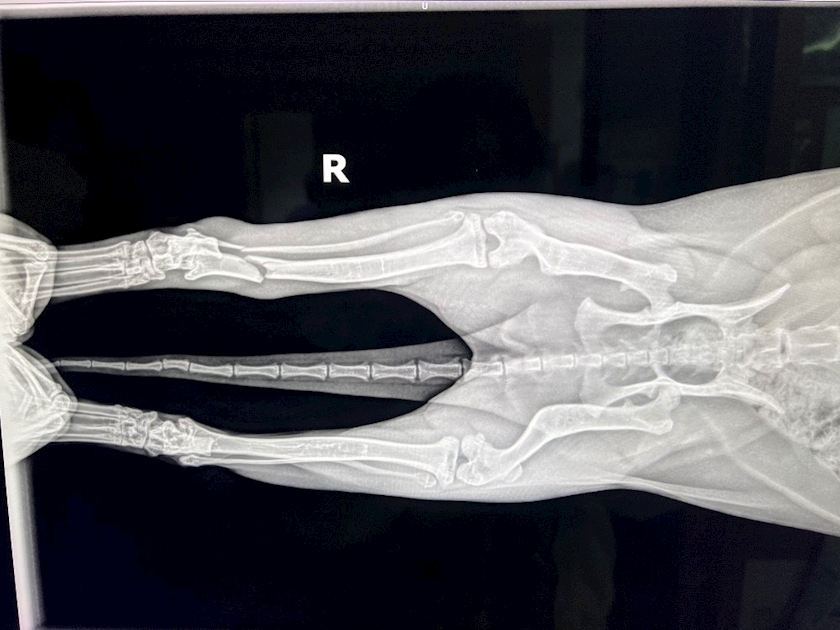

我が家の白猫ちゃんまさかの

骨折をしてしまいました。😭

キャットゲージから飛び降り

ポキっ

と。

折れてますねー🥲

難病の疑いが出て来ており、

オペもギブスも

ちょっと難しいらしいです😓😓

2ヶ月安静にして

自分の力で治す

治癒力に賭けましょう!